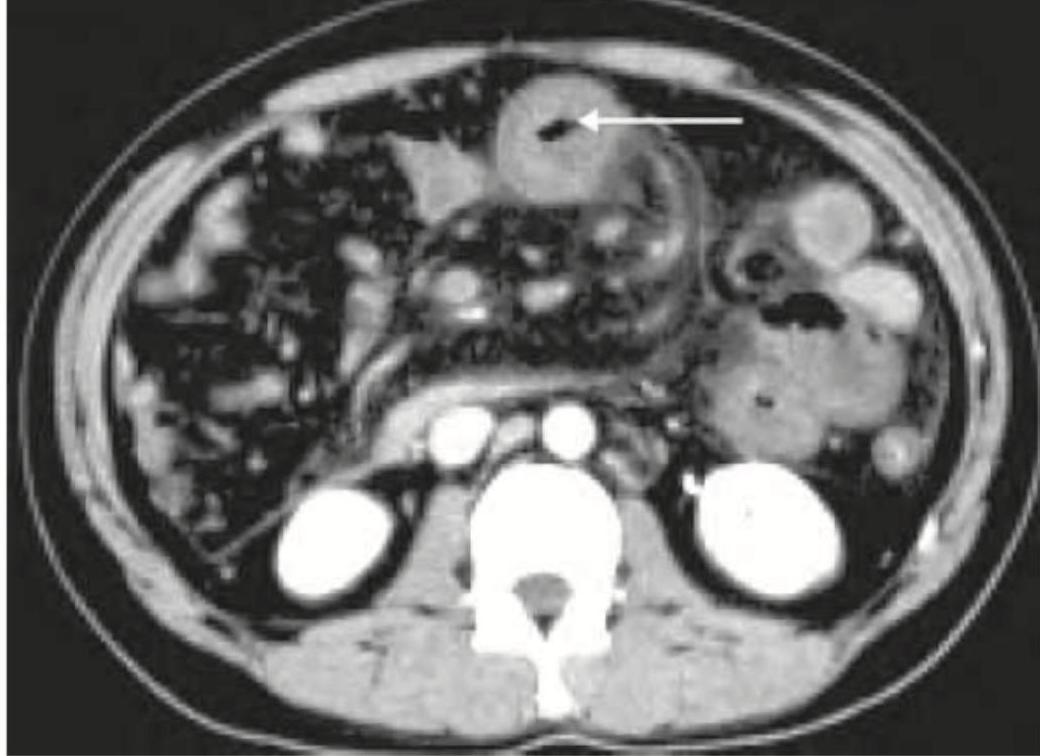

A 25-year-old patient underwent surgery for scoliosis correction. 5 days post-operatively he develops voluminous bilious vomiting. The given CT abdomen shows:

Question 12: A 25-year-old patient underwent surgery for scoliosis correction. 5 days post-operatively he develops voluminous bilious vomiting. The given CT abdomen shows:

- B. SMA syndrome (Correct Answer)

Explanation: ***SMA syndrome*** - The CT image shows significant **duodenal distention** proximal to the **superior mesenteric artery (SMA)**, characteristic of SMA syndrome. The arrow points to the **compressed third part of the duodenum** between the SMA and the aorta. - This condition is often seen post-scoliosis correction surgery due to rapid **spinal extension**, which can decrease the **aortomesenteric angle** and compress the duodenum, leading to **bilious vomiting**. *Paralytic ileus* - While ileus can cause vomiting and bowel distension, it typically involves **diffuse gaseous distension** of both small and large bowels without a discrete point of obstruction like the compressed duodenum seen here. - The clinical presentation of paralytic ileus post-operatively is more often characterized by generalized **absent bowel sounds** and abdominal distension, rather than specific bilious vomiting from high obstruction. *Pneumoperitoneum* - This refers to the presence of **free air in the abdominal cavity**, usually indicating a **visceral perforation**. - The provided CT image does not show any evidence of free air, and the presenting symptom of bilious vomiting is more indicative of obstruction. *Paravertebral abscess* - A paravertebral abscess would appear as a **fluid collection adjacent to the spine**, which is not depicted on this CT scan. - Clinical symptoms would likely include **fever, severe localized back pain**, and possibly neurological deficits, differing from the purely obstructive symptoms described.